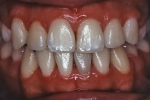

最良の解決策は、口腔外科的に開窓後、矯正歯科的に牽引し咬合に参加させることである。単に萌出させたと言うだけでなく、牽引後マルチブラケット装置を使用し、正常咬合を確立したケースの提示が求められている。

マルチブラケット終了時